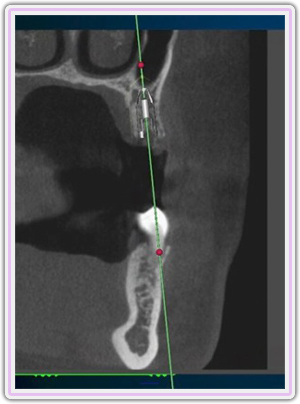

CT Planning For Upper Jaw Implant